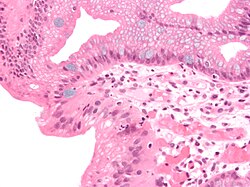

Barrettov jednjak označava prisutnost cilindričnog epitela u donjem dijelu jednjaka koji zamjenjuje normalni višeslojni pločasti epitel-tipičan je primjer za metaplaziju. Ovaj epitel koji nalikuje onome u želucu može bolje podnositi korozivno djelovanje želučane kiseline, međutim povećava opasnost od nastanka raka jednjaka.[7]

Imamo dva tipa metaplastičnih cilindričnih stanica: gastrične (želučane) koje su slične onima u želucu što se tehnički i ne smatra Barrettovim jednjakom i kolonične koje su nalik na epitel debelog crijeva. Obično se na biopsiji nađu oba tipa stanica. Metaplazija u kojoj stanice nalikuju onima iz debelog crijeva povezana je s genetski opterećenom populacijom.

Metaplazija je vidljiva na endoskopiji ali se uzorak mora pregledati mikroskopski da se utvrdi koji je tip stanica dominantan. Kolonička metaplazija je karakterizirana peharastim stanicama epitela i preduvjet je za postavljanje dijagnoze Barrettovog jednjaka.

Mikroskopska slika Barrettovog jednjaka. Alcian blue stain.